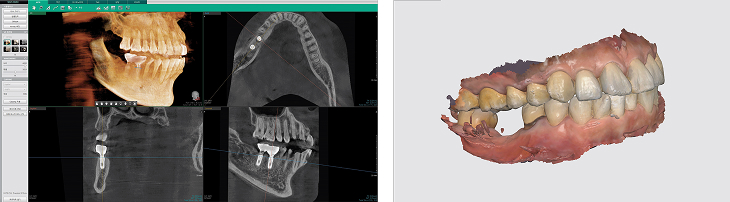

임플란트 시술 전 구강 스캐너로 채득한 구강스캔 데이터와 3D CT 영상을 이용해

치아, 잇몸, 신경, 혈관의 위치를 3차원으로 정밀하게 분석하여 안전한 식립 위치를 미리 파악합니다.

컴퓨터 디지털 시뮬레이션으로 임플란트 수술시 최적의 식립 위치, 각도, 깊이를 사전에 계획합니다.

시뮬레이션 결과를 바탕으로 제작된 네비게이션 수술 가이드를 이용하여 계획된 위치에 정확하게 임플란트를 식립합니다.

보철물 제작시에도 구강스캐너로 정밀하게 인상을 채득해 정확한 보철물을 만들게 됩니다.

임플란트 시술 전 구강스캔데이터와 3차원 CT영상을 이용해 입 안의 입체적 환경을 재현해 치아와 잇몸뼈, 신경의 위치까지 분석하여

임플란트가 들어갈 최적의 위치를 찾아 임플란트 치근을 정확하게 심습니다.

수술 전 미리 컴퓨터로 3D 분석 후 임플란트 시술에 들어가기 때문에 시술시간이 짧고, 수술 성공률이 높습니다.

• STEP 01 3D-CT 정밀진단

3차원 데이터를 바탕으로 환자분의 뼈, 잇몸, 신경 등을 종합적으로 고려하여 정밀진단을 실시합니다.

• STEP 02 컴퓨터 가상수술

정밀진단 데이터를 바탕으로 가상시뮬레이션을 통해 최적의 임플란트 식립위치, 각도, 깊이 등을 계획합니다.